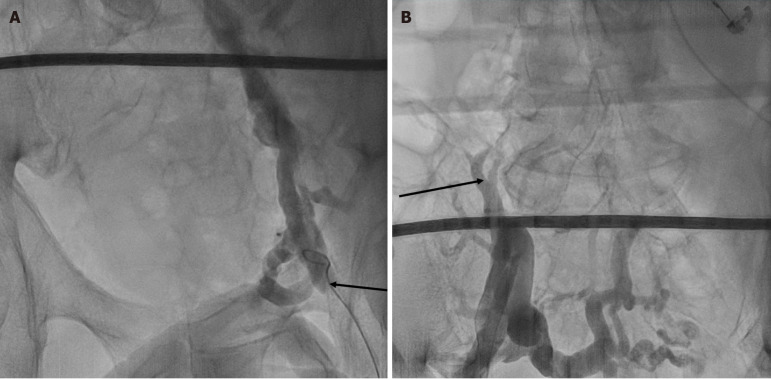

Case summary: A 76-year-old male with an extensive medical history notable for type 2 diabetes and severe peripheral vascular disease requiring vascular bypass surgery is identified to have paroxysmal AF. Given functional decline and worsening arrhythmia burden refractory to oral antiarrhythmics, an initial PVI ablation was attempted but failed as the catheter could not be advanced secondary to bilateral iliac vein occlusions. This necessitated a novel approach and a subsequent PVI ablation via the right IJ vein was successful without any complications. The success of this case highlights the feasibility of an IJ approach for PVI in patients where traditional access is not possible. This case can be used as a reference for other practitioners who may face similar challenges when attempting to perform PVI for AF or similar procedures requiring access to similar anatomical locations.